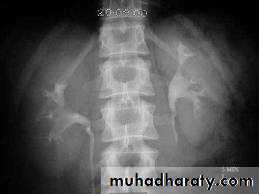

A. First a plain x-ray of the abdomen is taken before the injection of the contrast media, also known as A KUB (kidney, Ureter and Bladder). Calcification & stones may be obscured & missed by contrast media if plain film not takenfirst .

Interpretation of IVU films (what to look for?):

The kidneys:

Check their position (left kidney is usually higher).

Identify the whole of both renal outlines, look for any indentations or bulges:

Renal parenchymal width should be uniform(2-2.5cm)

measure renal lengths:

Normal length of adult kidney at IVU is 10-16cm. This is higher than in ultrasound due to image magnification.